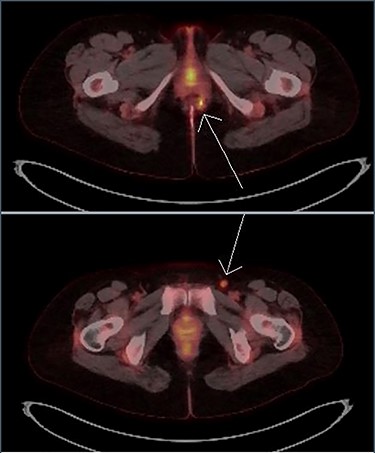

Imaging with MRI showed a trans-sphincteric fistula crossing the junction of the middle and lower third of the anal sphincters with a prominent left inguinal lymph node. A PET scan (Fig. 4) showed a moderately intense uptake in the left perianal region around the fistula with bilateral inguinal uptake (more so on the left side). Biopsy of the left inguinal node showed no evidence of lymphoma.

Transaxial PET scan. Upper view shows moderately intense uptake in the left perianal region. Lower view shows mild uptake in the left inguinal node.